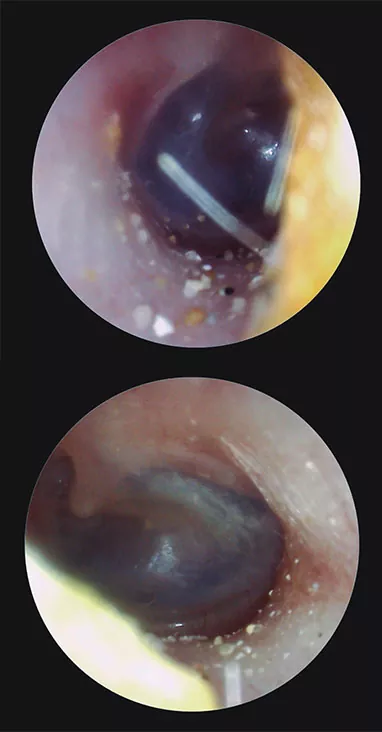

En los casos de oclusión o taponamiento, el grado de hipoacusia conductiva dependerá de la obstrucción total o parcial del CAE. Esta puede deberse a un tapón de cerumen (el más habitual), un cuerpo extraño (Fig. 3), un coágulo tras la hemorragia por erosión o herida de la piel del conducto, etc. Al eliminar la causa se recupera la audición.

Figura 3

Cuerpos extraños en el CAE: oído derecho e izquierdo de un paciente con arena en los conductos auditivos. En este caso el cuerpo extraño es muy pequeño y el paciente no refiere sintomatología.